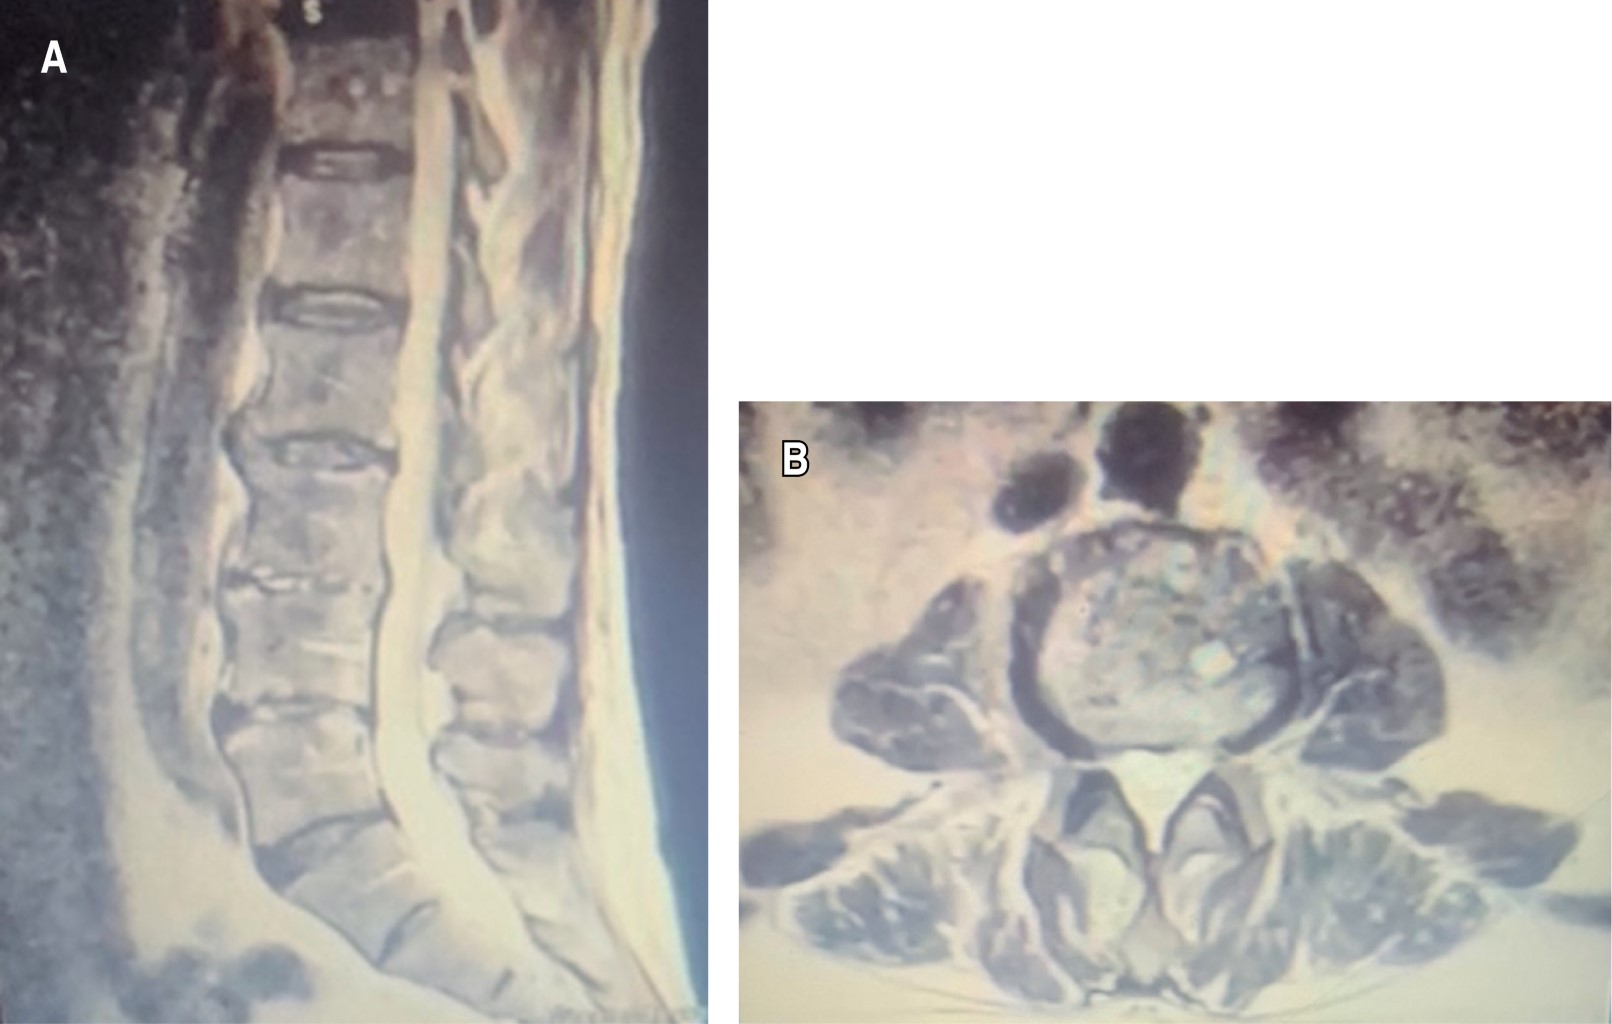

Figura 3